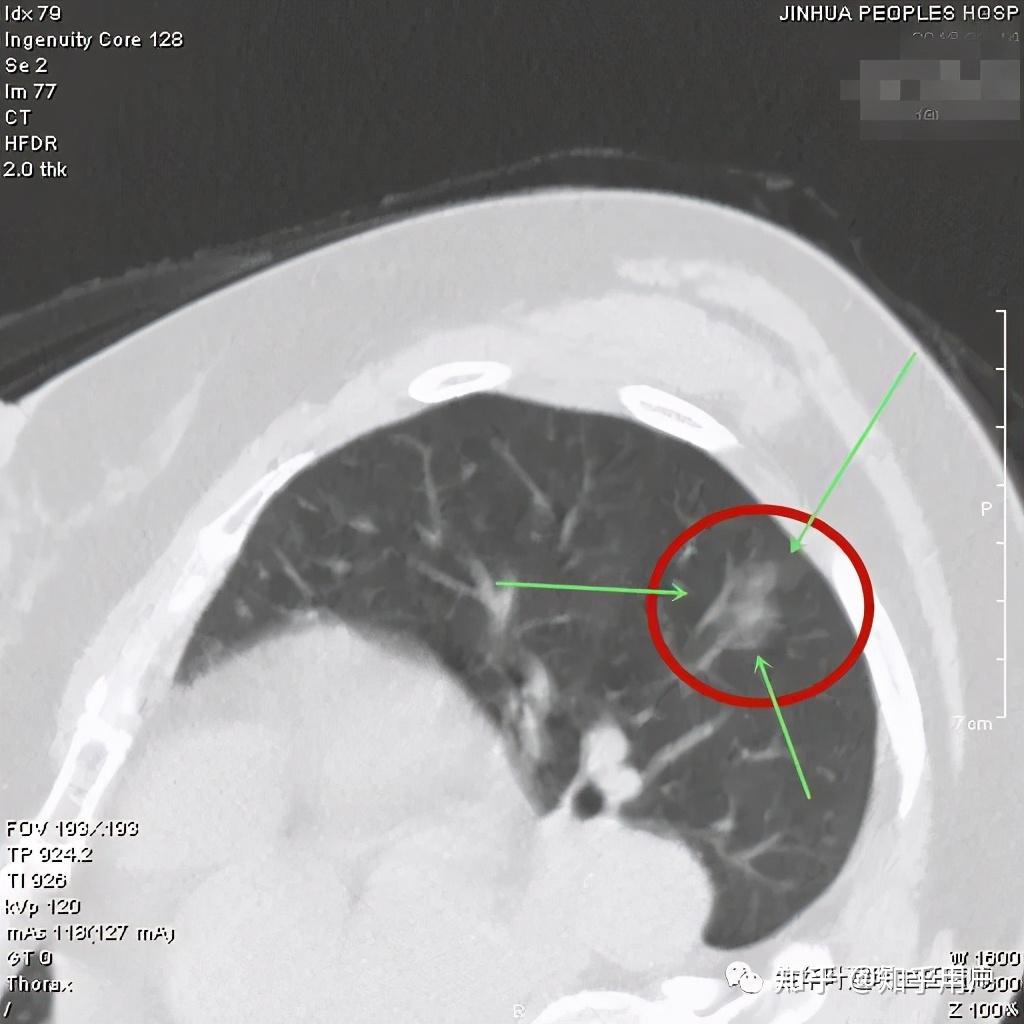

看着,非常不错,以后原位腺癌与非典型增生不是癌了,不需要手术了,至少不能按恶性肿瘤的方式进行手术了。这是好事!但真的到了临床上,如何把握,我看仍是前路漫漫,迷雾重重!我们先举几个例子,来看看影像上如何来区分AAH、AIS、MIA以及浸润性腺癌。下面的四幅CT图分别各是其中的一种,是我们术后有病理依据确诊的病例,你能分出哪张是哪种吗?

有没有高手能分辨出来?我是一头雾水,根本分不清到底哪个是哪种。都是纯磨玻璃结节,都是瘤肺边界清楚,大小都在1厘米左右或以下。现比如下面这四幅CT图也是分别为AAH、AIS、MIA以及浸润性腺癌(贴壁型),你能分得清楚哪幅图是哪种吗?

这几乎就是四胞胎,长的没什么区别,但病理类型天差地别。现在把AAH与AIS剔除出恶性肿瘤后,更是差别巨大了,是癌与非癌的区别了,但没有手术切除病检的情况下,你如何来区分?